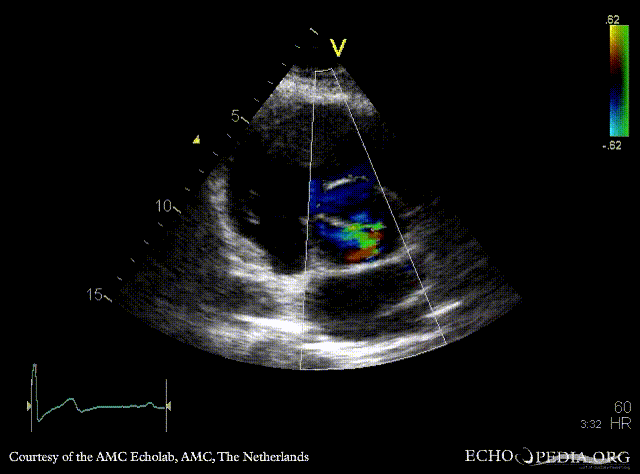

PSAX with Color Doppler: moderate aortic regurgitation Suprasternal view